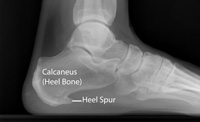

Although many people with plantar fasciitis have heel spurs, spurs are not the cause of plantar fasciitis pain. One out of 10 people has heel spurs, but only 1 out of 20 people (5%) with heel spurs has foot pain. Because the spur is not the cause of plantar fasciitis, the pain can be treated without removing the spur.

X-rays provide clear images of bones. They are useful in ruling out other causes of heel pain, such as fractures or arthritis. Heel spurs can be seen on an x-ray.